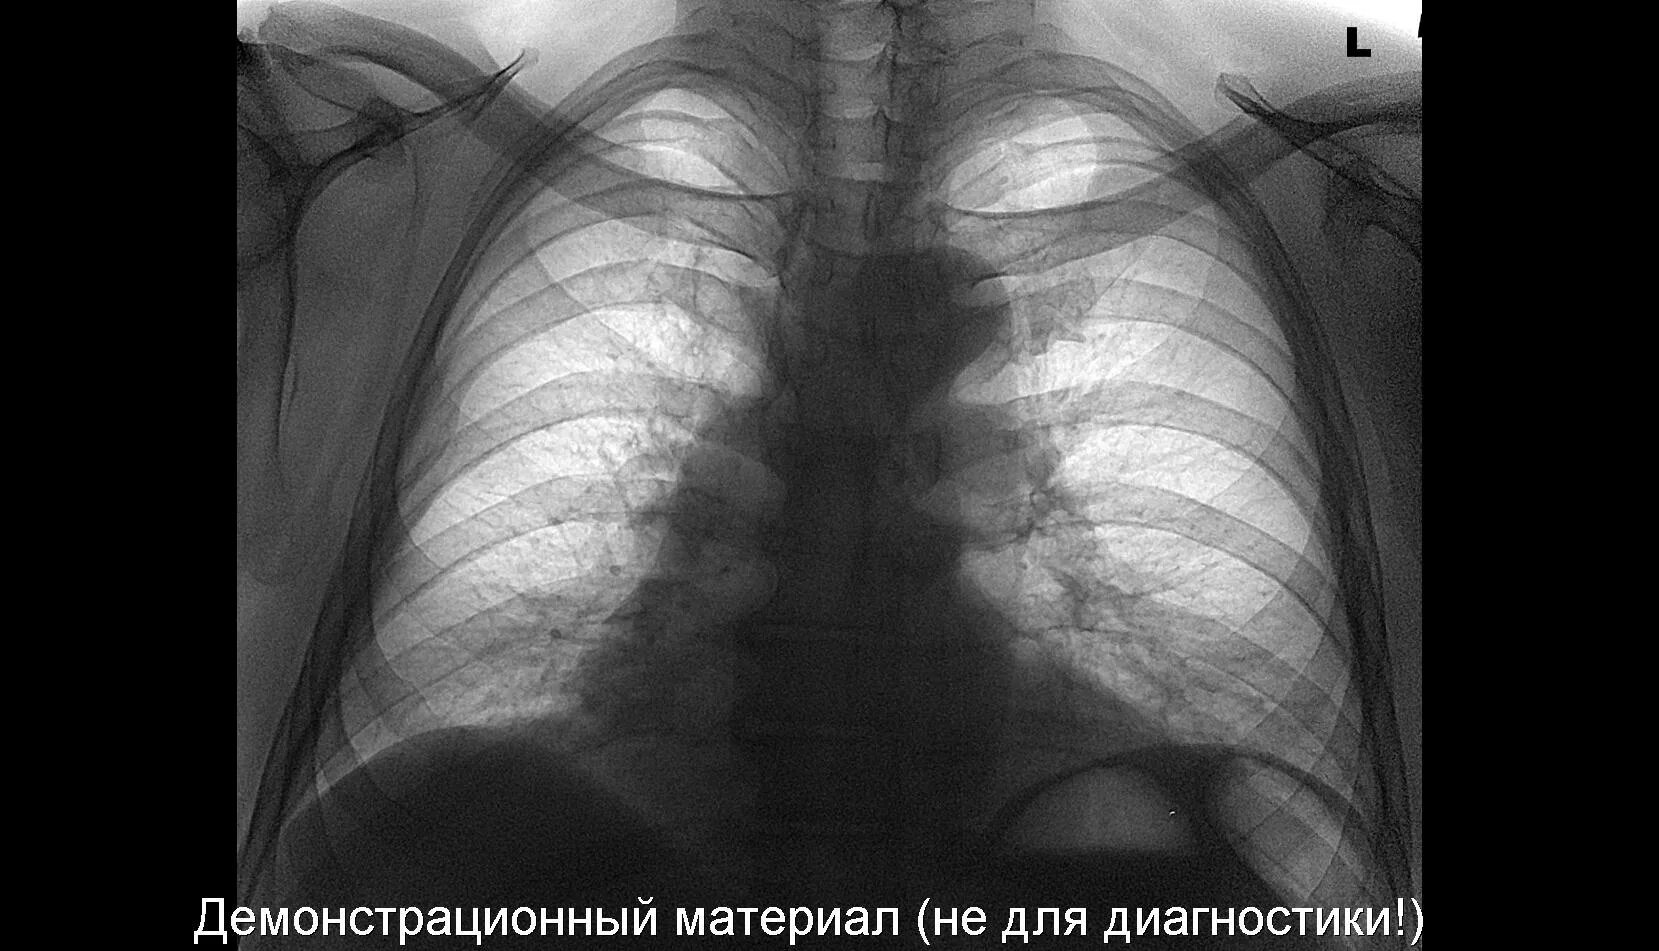

Что значит аорта уплотнена на флюорографии